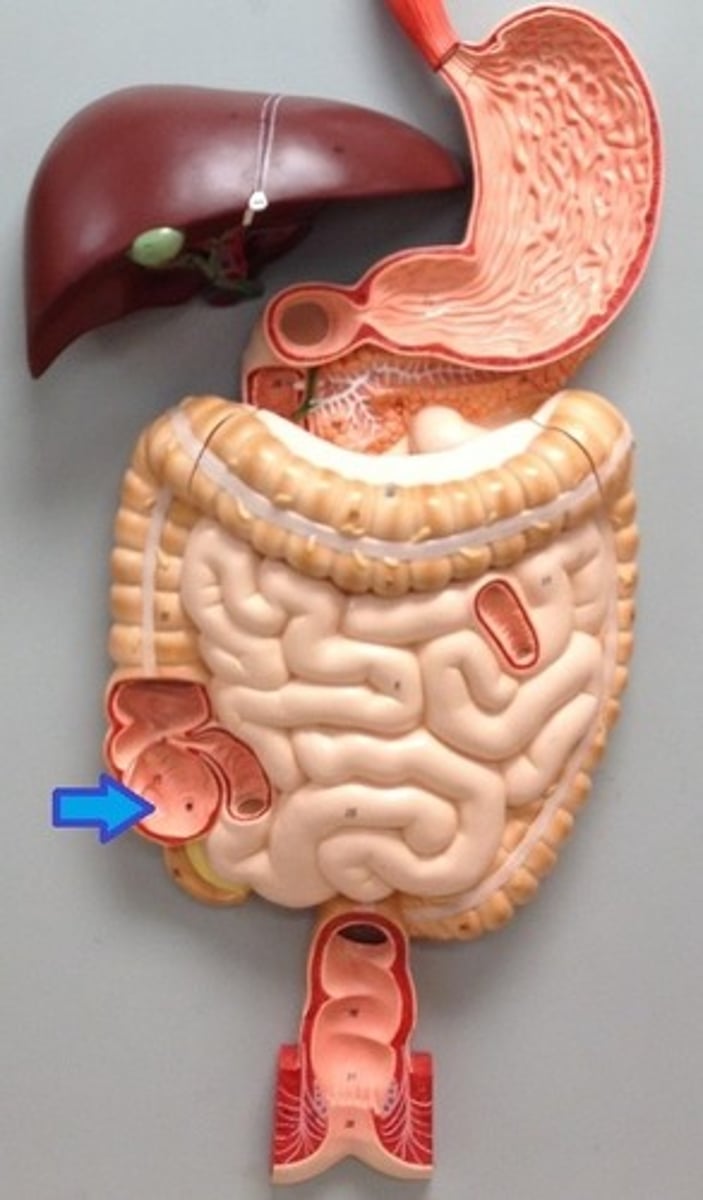

large intestine

cecum

cecum

ascending colon

transverse colon

descending colon

sigmoid colon

illeocecal valve

Apendix

liver

Gallbladder

pancreas

spleen